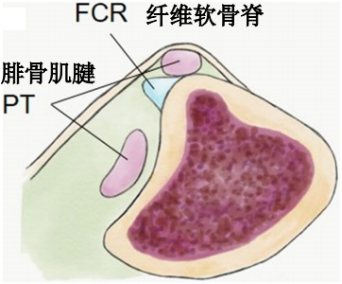

纤维软骨脊(FCR):腓骨外踝窝的外侧缘有一纤维软骨形成的缘,构成了窝的结构。该纤维软骨脊近端明显,向远端渐变小,使得沟的整体深度增加了2-4mm,且形状更适于容纳腓骨肌腱,从而促进应力分散。

腓骨上支持带(SPR):起于腓骨外侧面和腓骨外踝窝,绕过腓骨肌腱后止于跟骨和跟腱外侧。SPR没有直接牢固固定于纤维软骨脊,而是与腓骨外侧面的骨膜融合。

I型:最常见(51%),腓骨上支持带(SPR)和骨膜仍保持联系,骨膜从外踝上撕脱,腓骨肌腱滑向前方使骨膜和外踝分离。

Ⅱ型:(33%)纤维软骨脊连同腓骨上支持带(SPR)一起和外踝分离,腓骨肌腱向前脱位。

Ⅲ型:(16%)纤维软骨脊连同部分外踝骨质和腓骨上支持带(SPR)一起与外踝分离,肌腱脱位至骨折块下方。

IV型:Oden1987年在此基础上外,还有少见的第IV型,表现为腓骨上支持带(SPR)的完全撕脱或断裂,并且肌腱移位于支持带的外表面。